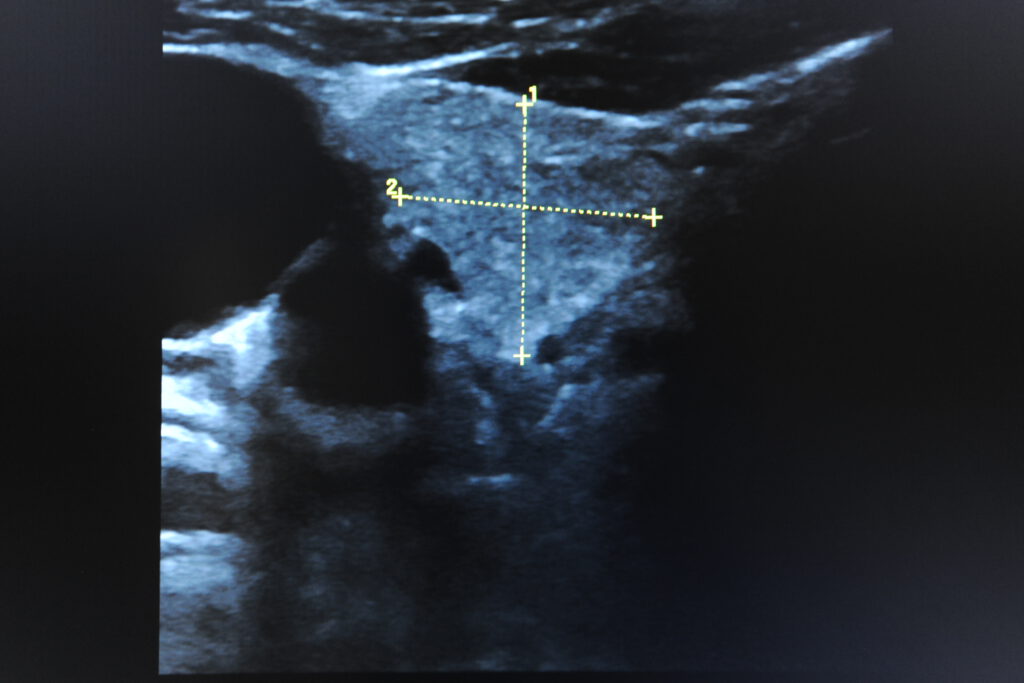

Schilddrüse,

- Komplett-Check: (ausgiebige Anamnese, körperliche Untersuchung, Hautkrebsscreening, Stuhluntersuchung auf Mikroblutungen, Urinuntersuchung, grosse Blutuntersuchung, Ultraschall vom Bauch, Herz, hirnversorgende Gefäße, Schilddrüse, Lungenfunktionsuntersuchung, EKG, ggf. Belastungs EKG)